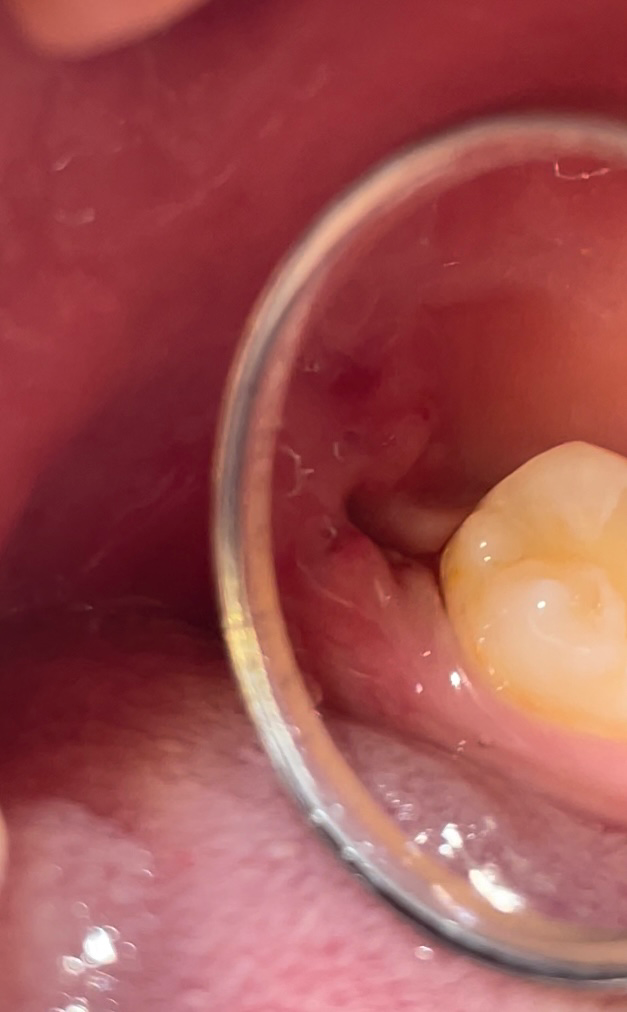

사랑니 실밥 제거후 음식찌꺼기 빼는 방법? (사진첨부)

사랑니 실밥 제거후 (일주일 후) 구멍이 보이는데... 먹을때 음식찌꺼기가 들어갈까봐 무섭네요.

• 1번 째 사진